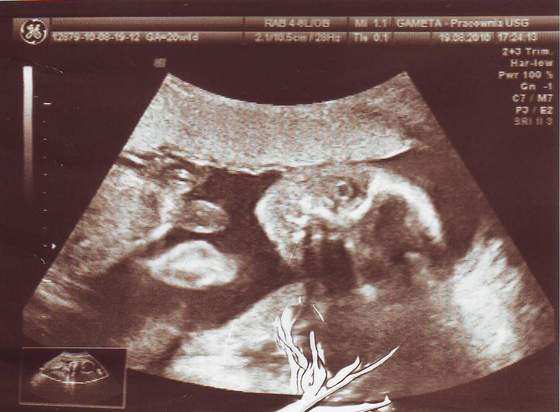

Moja córcia końcem 17 tygodnia:*